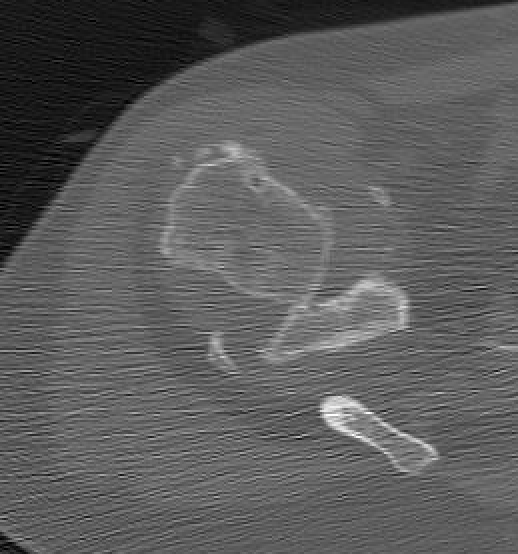

CT

Assess bone stock / glenoid bone loss / Hill Sachs lesions

Chronic shoulder dislocation with large Hill Sachs and significant glenoid deficiency